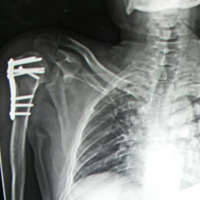

Case:17 Bilateral Fracture Dislocation

Known case of Epilepsy in 45-year-old Mason treated with open reduction & internal fixation with philos plate & locking screws bilaterally.

Right side Pre-Op

Right side Post-Op